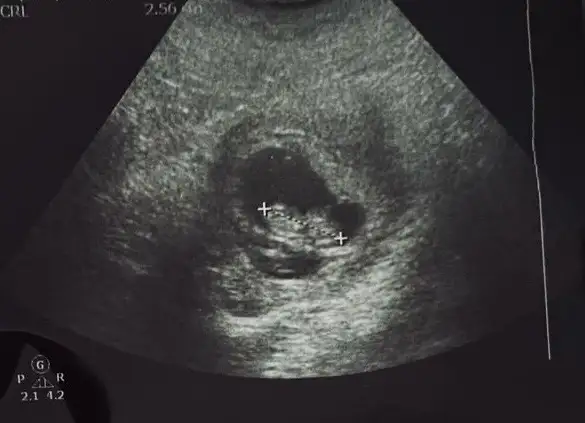

banada bakarmısınız 14 haftalık

Merhabalar 9+2 sizce cinsiyet nedir 🌸